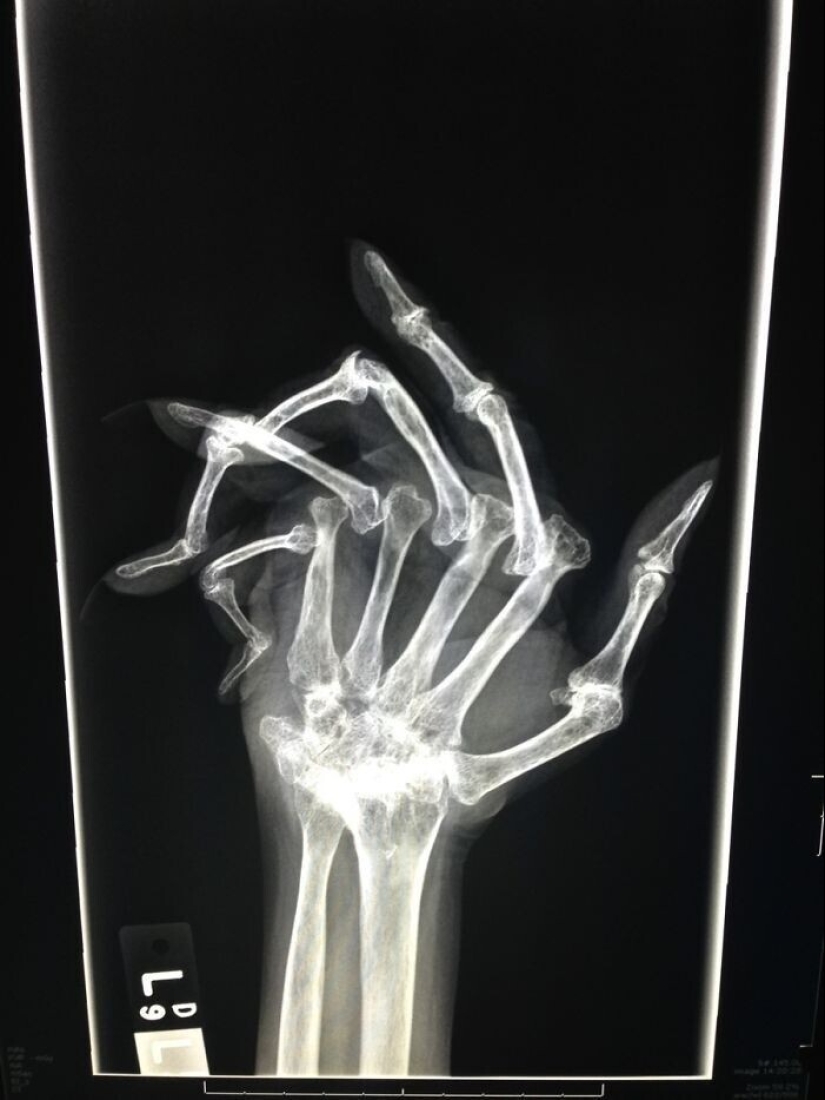

La muñeca en la radiografía se ve un poco de miedo